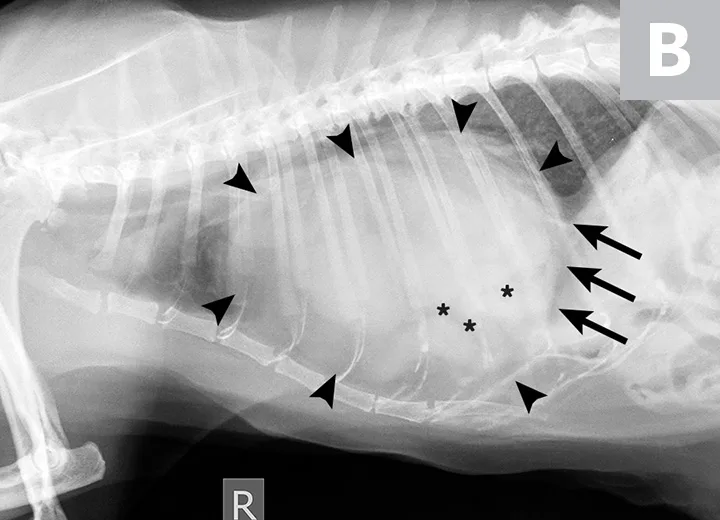

Joker was kept in a calm environment and continued to receive oxygen supplementation overnight. The following day, he was placed under general anesthesia. He was premedicated with hydromorphone (0.05 mg/kg IV) and acepromazine (0.02 mg/kg IV), induced with propofol (IV) to effect, and maintained with an isoflurane inhalant carried in oxygen. An exploratory laparotomy was performed, and a diagnosis of PPDH was confirmed (Figure 2; see Treatment at a Glance).

Intraoperative images. The PPDH can be visualized after ventral midline laparotomy and removal of the falciform ligament (A). The PPDH contains the hepatobiliary tract and a portion of the small intestine and omentum. Following reduction of the GI contents and the herniated portion of the omentum, the hernia ring can be visualized, and the hepatobiliary tract remains in the PPDH (B).